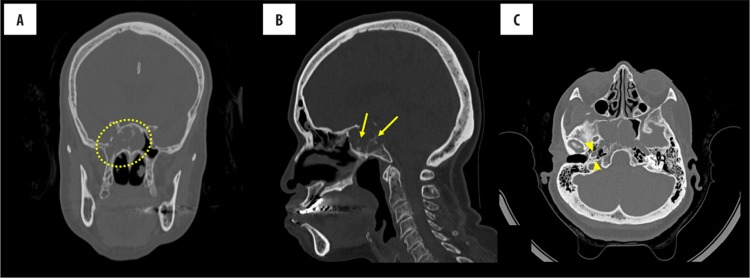

獲得鼻竇的CT掃描(圖1)顯示在中線蝶竇內(nèi)有一個(gè)大的可膨脹的侵蝕性腫塊。它的全部尺寸都超過(guò)3厘米。腫塊是等密度的,完全充滿蝶竇,從下方侵蝕蝶竇并延伸至右側(cè)氣化的翼。左側(cè)翼突也氣化了,但不能容納腫塊。腫塊也侵蝕到斜坡的上部,并延伸到后顱窩。它有分散的鈣化,這可能代表了原生骨的侵蝕。在使用14 ml造影劑(Magnevist)前后進(jìn)行的腦部MRI顯示一個(gè)大的腫塊,涉及斜坡和蝶竇,主要在右側(cè),具有與CT相同的特征性發(fā)現(xiàn)(圖2)。腫塊在T2加權(quán)像上呈高信號(hào),在T1加權(quán)像上呈輕度低信號(hào),呈不均勻強(qiáng)化。

圖1:鼻腔和副鼻竇的CT檢查無(wú)對(duì)比。蝶竇和蝶鞍中心有一個(gè)大的等密度腫塊(A),伴有散在的鈣化(B中的箭頭)。腫塊充滿蝶竇,向下侵蝕蝶竇。它延伸到右側(cè)充氣翼狀胬肉(C中的箭頭)。隨著前庭池的消失和兩個(gè)海綿竇的受累,也可延伸到后顱窩。